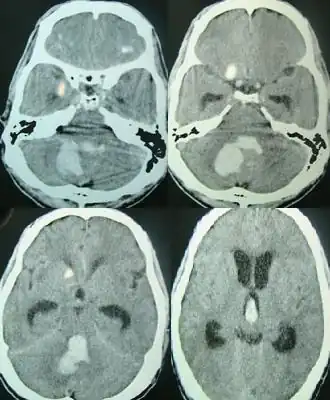

![]() Внутримозговое кровоизлияние в задней черепной ямке | |

Методом выбора в диагностике внутримозгового кровоизлияния является компьютерная томография головного мозга, позволяющая не только определить наличие внутримозговой гематомы, но и оценить её локализацию, распространённость и объём, выраженность отёка мозга и степень дислокации. Для диагностики небольших гематом в стволе мозга и изоденсивных веществу головного мозга («несвежих») гематом предпочтительна магнитно-резонансная томография.